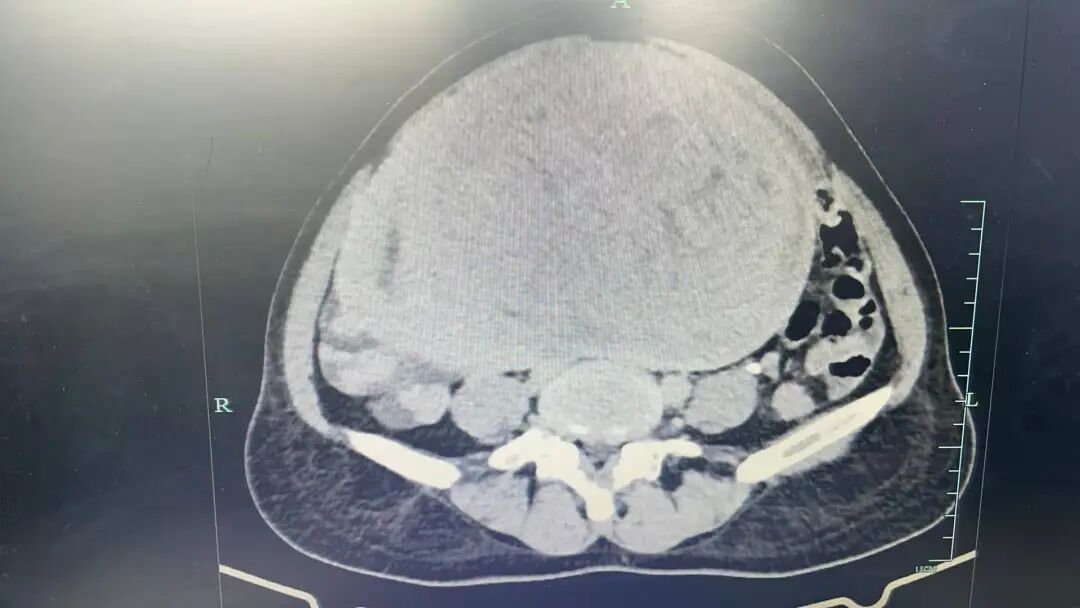

“影像显示这个肿瘤几乎填满了整个腹腔,实际情况可能更为复杂,若持续生长,可能压迫膀胱、输尿管、肠道等重要脏器,引发肾积水、肾损害、肠道病变等一系列并发症。”

结合症状及检查,考虑肿瘤来源于子宫,因肿瘤体积大、患者贫血严重,术中风险及手术难度均较高。术前医院组织多学科病例讨论,完善相关准备工作并制定应急预案。

在外科与妇科协同配合下,为患者实施了盆腔肿瘤切除术,术中取出的一个类圆形实体肿块,直径约25cm,重量达6斤多(与胎儿大小相近),手术过程顺利。患者术后恢复良好,现已顺利出院。